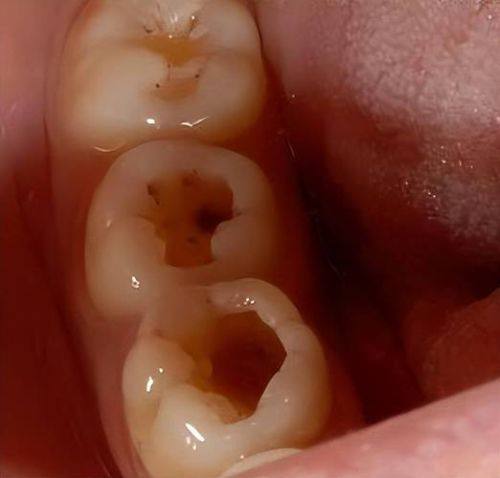

对于特别多有龋齿困扰的人来说,“龋齿治疗会出血吗”是一个令人担忧的问题。毕竟,口腔内的治疗总是让人有些紧张,害怕出现意外状况。其实,龋齿治疗是否会出血需要分情况来看。了解这个问题的答案,不仅能让我们在治疗前做好心理准备,还能避免不必要的恐慌。接下来,我们就一起深入揭秘龋齿治疗过程中的真实情况。

根管治疗是治疗急性牙髓炎或重度龋齿的常见方法。当龋齿发展到一定程度,细菌感染到牙髓,引起牙髓炎症时,根管治疗就派上用场了。它主要是通过清除根管内的炎症牙髓和坏死物质,并进行适当消毒,充填根管,以去除根管内容物对根尖周围组织的不良刺激,防止发生根尖周病变或促进根尖周病变的愈合。

综上所述,“龋齿治疗会出血吗”这个问题的答案取决于牙髓腔内神经是否坏死。如果神经未坏死,治疗可能会出血,这是正常现象;如果神经已坏死,治疗一般不会出血。在治疗期间,要注意口腔护理,避免食用不合适的食物。同时,选择正规医疗机构进行治疗是非常重要的。希望大家都能对龋齿治疗有更清晰的认识,遇到问题及时就医,保护好自己的口腔健康。